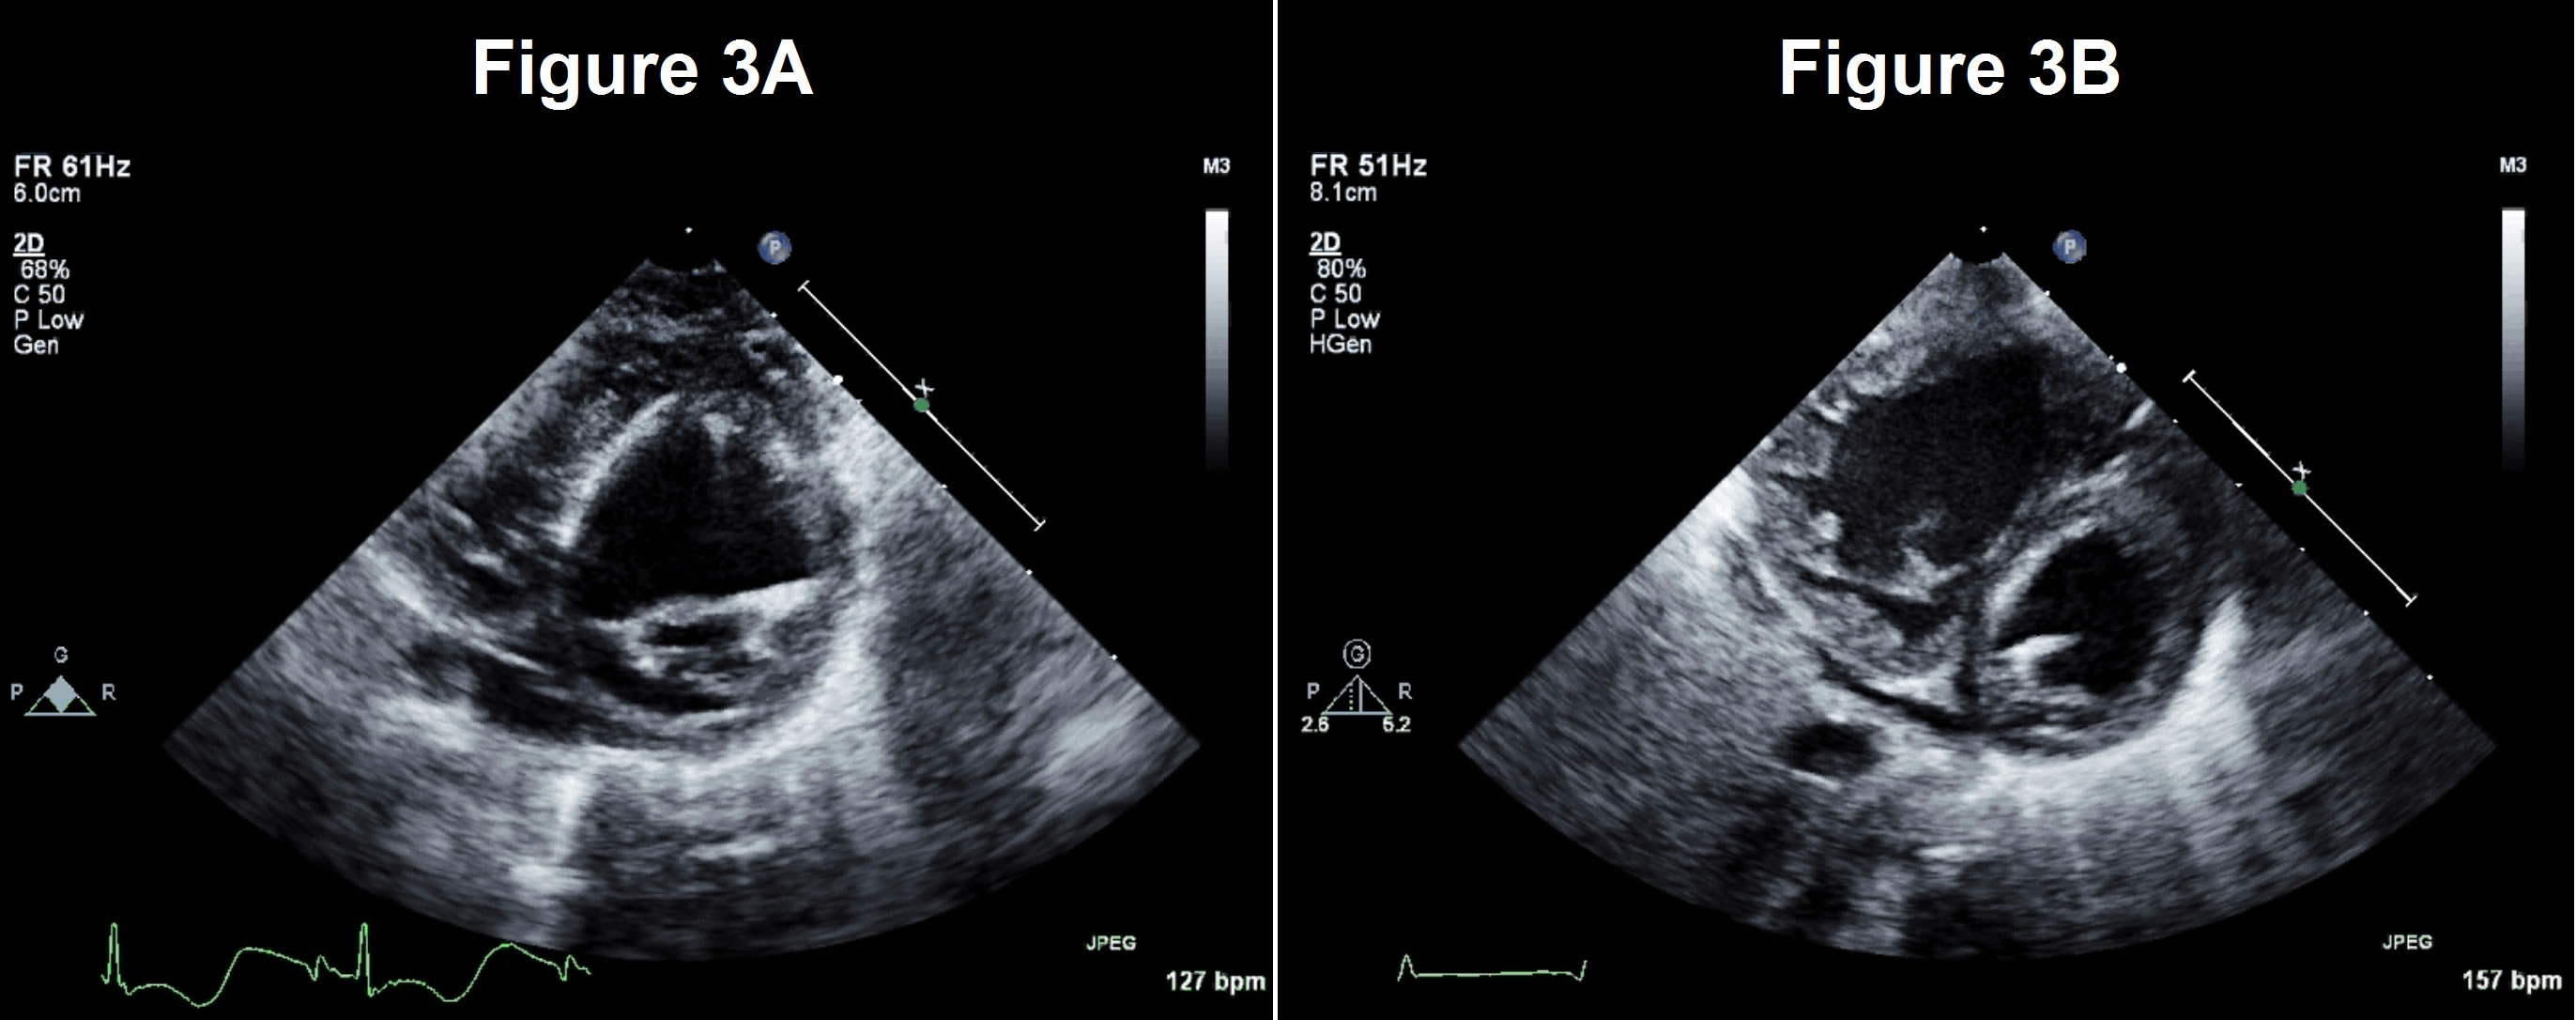

Figures 3A/3B

Patient's heart in parasternal short-axis views, before (A) and after (B) stage 1

This patient had a hypoplastic mitral valve (Z-score -2.4), a unicommisural aortic valve and significant EFE (Figures 2a and 3a). He underwent a stage 1 single-ventricle palliation. Subsequent studies show a significant decrease in LV size and more pronounced EFE after decompression, suggesting that the left heart was incapable of supporting systemic circulation (Figures 2b and 3b). The patient is currently doing well.